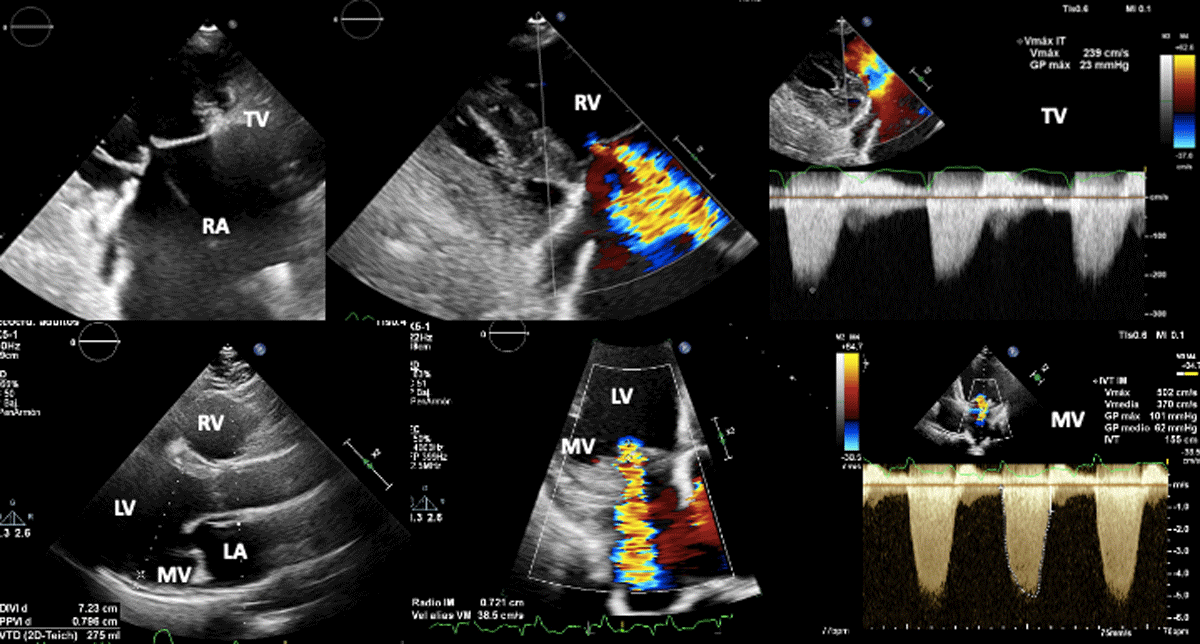

3.3.6 Valvular disease

Dilated cardiomyopathy is the most severe manifestation of ChD and can contribute to the presence of functional valve abnormalities such as mitral or tricuspid regurgitation (secondary regurgitation) [42].

In secondary mitral regurgitation (SMR), the valve leaflets and chordae are structurally normal and mitral regurgitation results from an imbalance between closing and tethering forces secondary to alterations in LV and LA geometry [60]. In ChD, severe LV dilatation has been associated with the presence of mitral valve regurgitation due to a dilatation of the mitral annulus. Also, in the case of wall motion disorders of the inferior and/or inferolateral segments, posterior leaflet tethering, despite almost normal LV size and ejection fraction, can be the mechanism, with a similar appearance to ‘ischemic MR’ [60].

In addition, ChD may also have a direct effect on the valves and be the direct cause of valvular heart disease (primary regurgitation). The pathogenesis of ChCM has not been completely elucidated, though the parasite-driven inflammatory reaction and the adverse host immune response are likely factors [61]. Resulting myocarditis, which is a feature of ChCM, frequently affects the papillary muscles leading to valve dysfunction, mainly regurgitation. This has been also reported as the main cause for the mitral valve prolapse seen in these patients [61].

The principal mechanism of tricuspid regurgitation in ChD is as a consequence of left-ventricular dysfunction. In some cases it may be secondary to pressure and/or volume overload mediated RV dilatation.

The echocardiographic criteria to define severe mitral and tricuspid regurgitation do not differ from those used usually in both primary and secondary mitral and tricuspid regurgitation (Figure 5) (60).

Figure 5

Biventricular dysfunction in a patient with Chagas disease. Superior figures show non coaptation of the tricuspid valve (due to right ventricular dilation) and its consequent functional regurgitation. Lower figures show mitral regurgitation secondary to left ventricular dysfunction.

Image: Mariana Corneli. Reproduced with permission of the photographer.